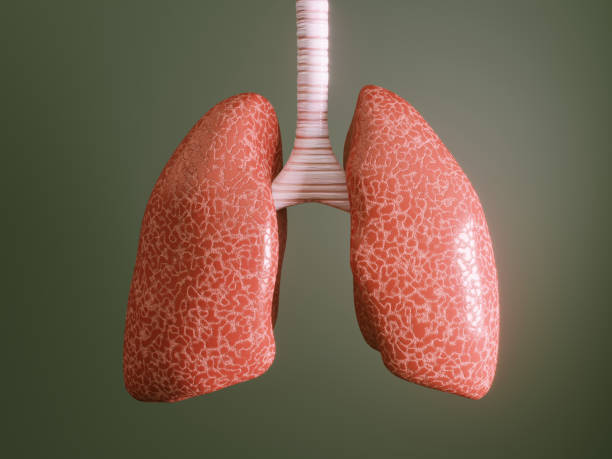

천식은 기관지의 염증과 경련으로 인해 기침, 숨이 차고 가슴이 답답한 등의 호흡곤란 증상을 보이는 만성적인 폐질환입니다. 이러한 천식 환자들은 종종 목이 간질간질하고 마른 기침이 나타날 수 있습니다.

천식의 원인은 다양하지만, 대개는 호흡기에 접촉한 알레르기성 물질이나 공기 오염 물질에 대한 반응으로 인한 것입니다. 이러한 반응으로 인해 호흡기의 기관지가 수축하고 염증이 생겨 호흡 곤란 증상이 나타납니다. 이때, 기침은 호흡기를 청소하고 비염, 기관지염 등으로 인한 분비물을 제거하는 역할을 합니다.

하지만, 천식 환자의 경우 호흡기의 염증과 경련으로 인해 기침이 잘 제어되지 않아 목이 간질간질하고 마른 기침이 나타나게 됩니다. 또한, 천식 환자는 호흡 곤란으로 인해 호흡을 하려고 할 때 공기가 막혀 기침을 유발할 수 있습니다. 따라서, 천식 환자가 목이 간질간질하고 마른 기침이 나타날 경우 즉각적인 치료가 필요합니다. 천식은 약물 치료와 호흡 운동 치료 등으로 적극적으로 치료가 가능하며, 적절한 치료로 호흡기 증상을 완화시킬 수 있습니다.